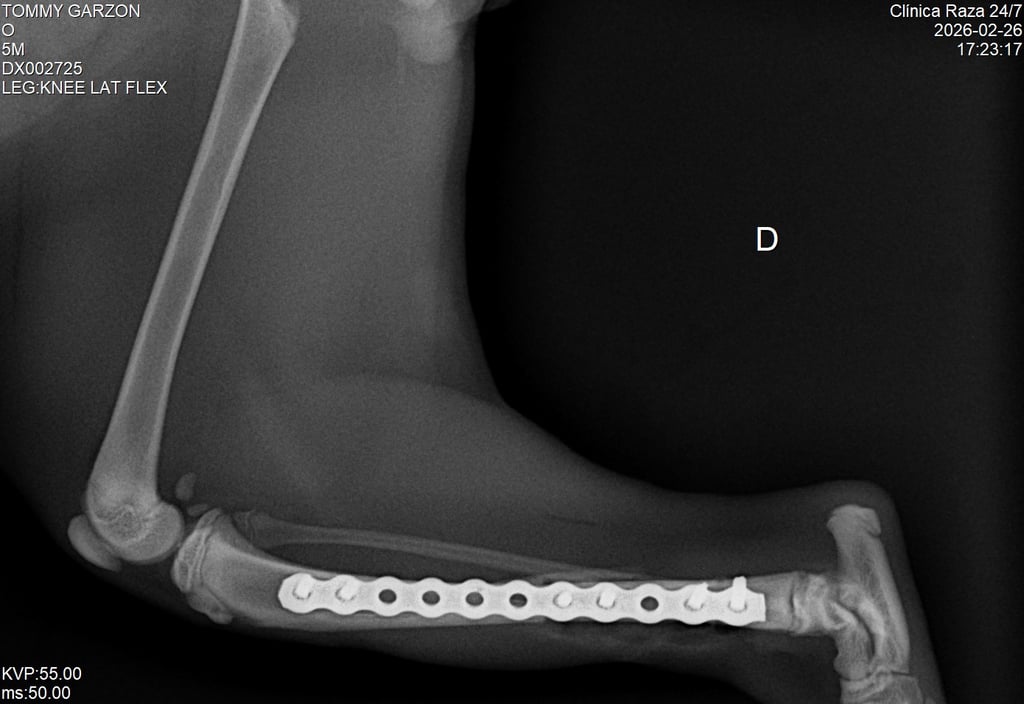

Cuando una fractura no puede tratarse únicamente con inmovilización, el veterinario puede recomendar una cirugía ortopédica. Este procedimiento permite estabilizar el hueso utilizando implantes especializados que ayudan a mantener la estructura ósea en la posición correcta durante el proceso de cicatrización.

En la ortopedia veterinaria moderna se utilizan diferentes sistemas de fijación que permiten una recuperación más rápida y segura para el paciente. Entre ellos se encuentran placas, tornillos y otros dispositivos diseñados específicamente para cirugía veterinaria.